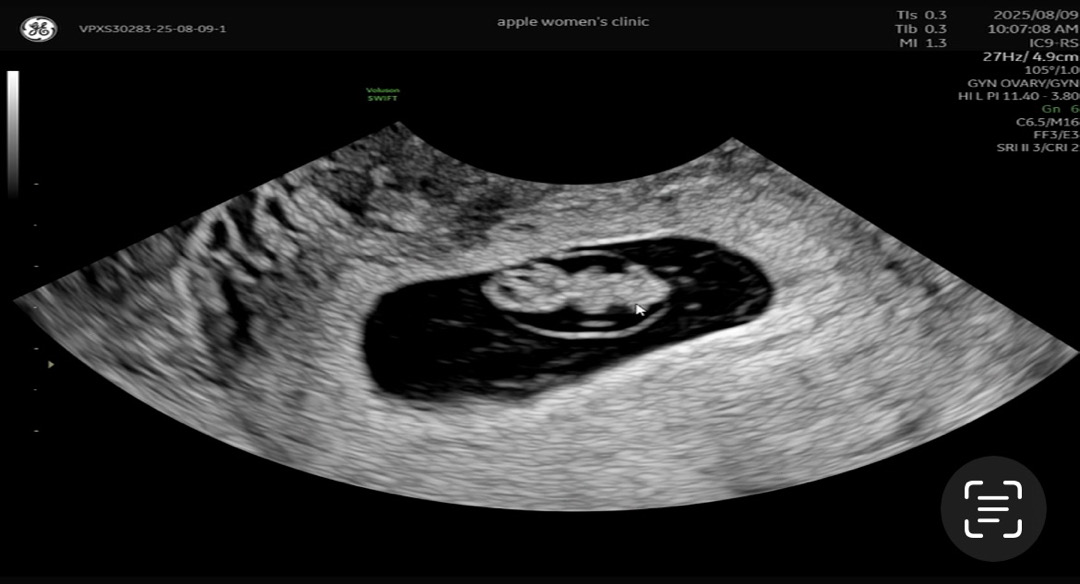

전 젤리곰 생각도 못하다가 초음파 봤는데 젤리곰이더라구요. 이때가 8주 5일이엇어요. 둥이들 각각 보니 진짜 젤리곰이어서 넘 귀여웟던☺️

8주1일날차 젤리곰 보고 9주6일차 조금 더 커진 젤리곰 봤어요 !! ㅎㅎ 사진은 8주 1일차 젤리곰 ㅎㅎ